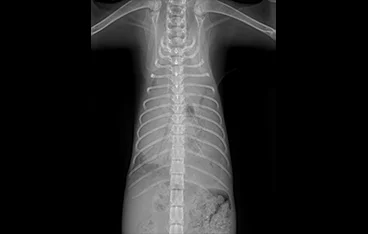

• 횡격막탈장

• 횡격막탈장 수술 전

횡격막탈장 수술 후